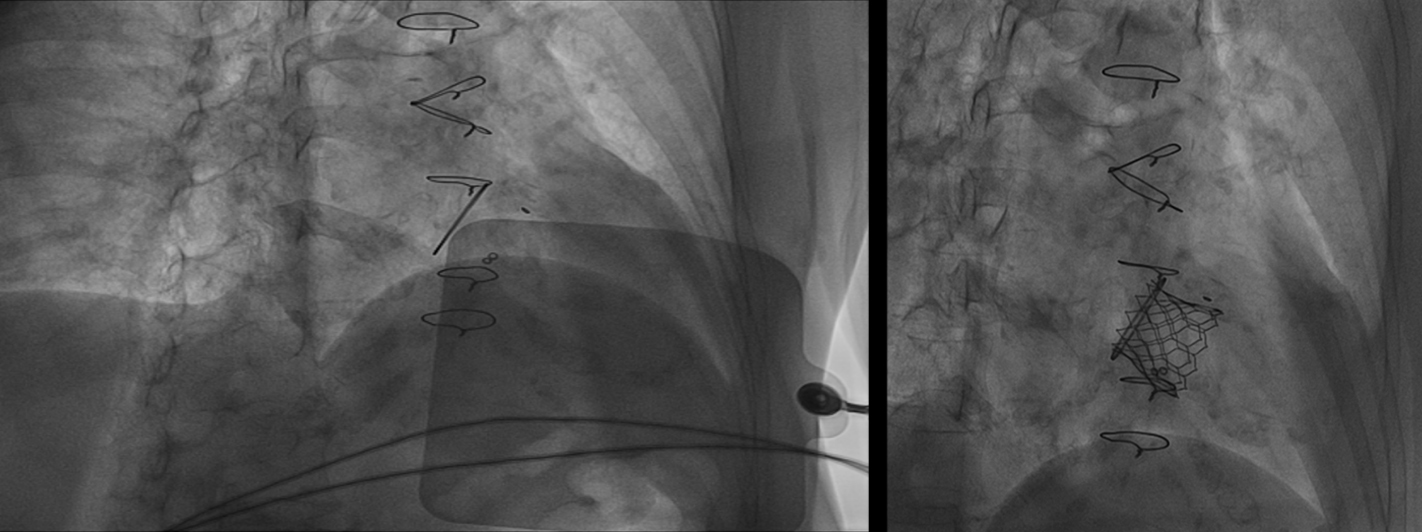

近日,兰大二院心血管内科成功为一名二尖瓣人工生物瓣置换术后前叶脱垂并重度关闭不全的患者实施了经导管二尖瓣瓣中瓣植入术。

患者为72岁女性,13年前行二尖瓣瓣膜置换术,近1年出现活动后胸闷、气短,心脏彩超提示二尖瓣生物瓣前叶脱垂并重度关闭不全,肺动脉重度高压(84mmHg),考虑原生物瓣膜衰败,因再次外科换瓣手术难度大、风险高,经MDT讨论后决定行经导管二尖瓣瓣中瓣植入术。在麻醉科、心脏功能检查科的全力配合下,手术由心血管内科一病区孙守刚主任主导完成。术后,患者心功能得到了根本改善,第二天即可下地步行,术后第四天康复出院。

经导管心脏瓣膜瓣中瓣植入术是新兴的介入治疗技术,手术创伤小、患者恢复快。此次手术的成功开展标志着兰大二院心脏瓣膜病介入治疗取得了新的进展,为广大瓣膜性心脏病患者带来了更多的选择。